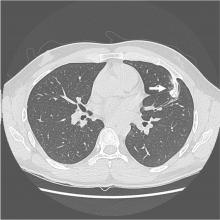

This video shows the case of a forty-year-old man who presented for evaluation of several months of anterior chest wall pain. Cross sectional imaging demonstrated a calcified anterior fourth rib lesion arising from the posterior table and projecting inward into the left hemithorax, measuring up to 3.8 cm (Figure 1).

Physical examination was notable for an outwardly normal chest wall with no palpable abnormalities. The patient carried a history of multiple exostoses syndrome with multiple prior resections of long bone osteochondromas from infancy until 20 years of age (1). His family history was significant for multiple first-degree relatives with multiple exostoses syndrome.